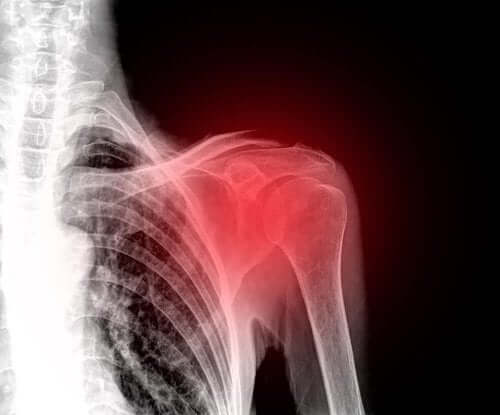

Først vil en lege utføre en fysisk undersøkelse for å diagnostisere bristen i rotatorkappen. I løpet av undersøkelsen vil de se nærmere på evnen til å bevege skulderen, styrken og eventuelle leddsmerter.

Tilsvarende utfører de ofte komplementære tester som ultralyd eller magnetresonanstomografi. Dette skyldes at ultralyd lar dem evaluere senene og musklene når du beveger deg. I tillegg er det en rimelig og ikke-invasiv undersøkelse.